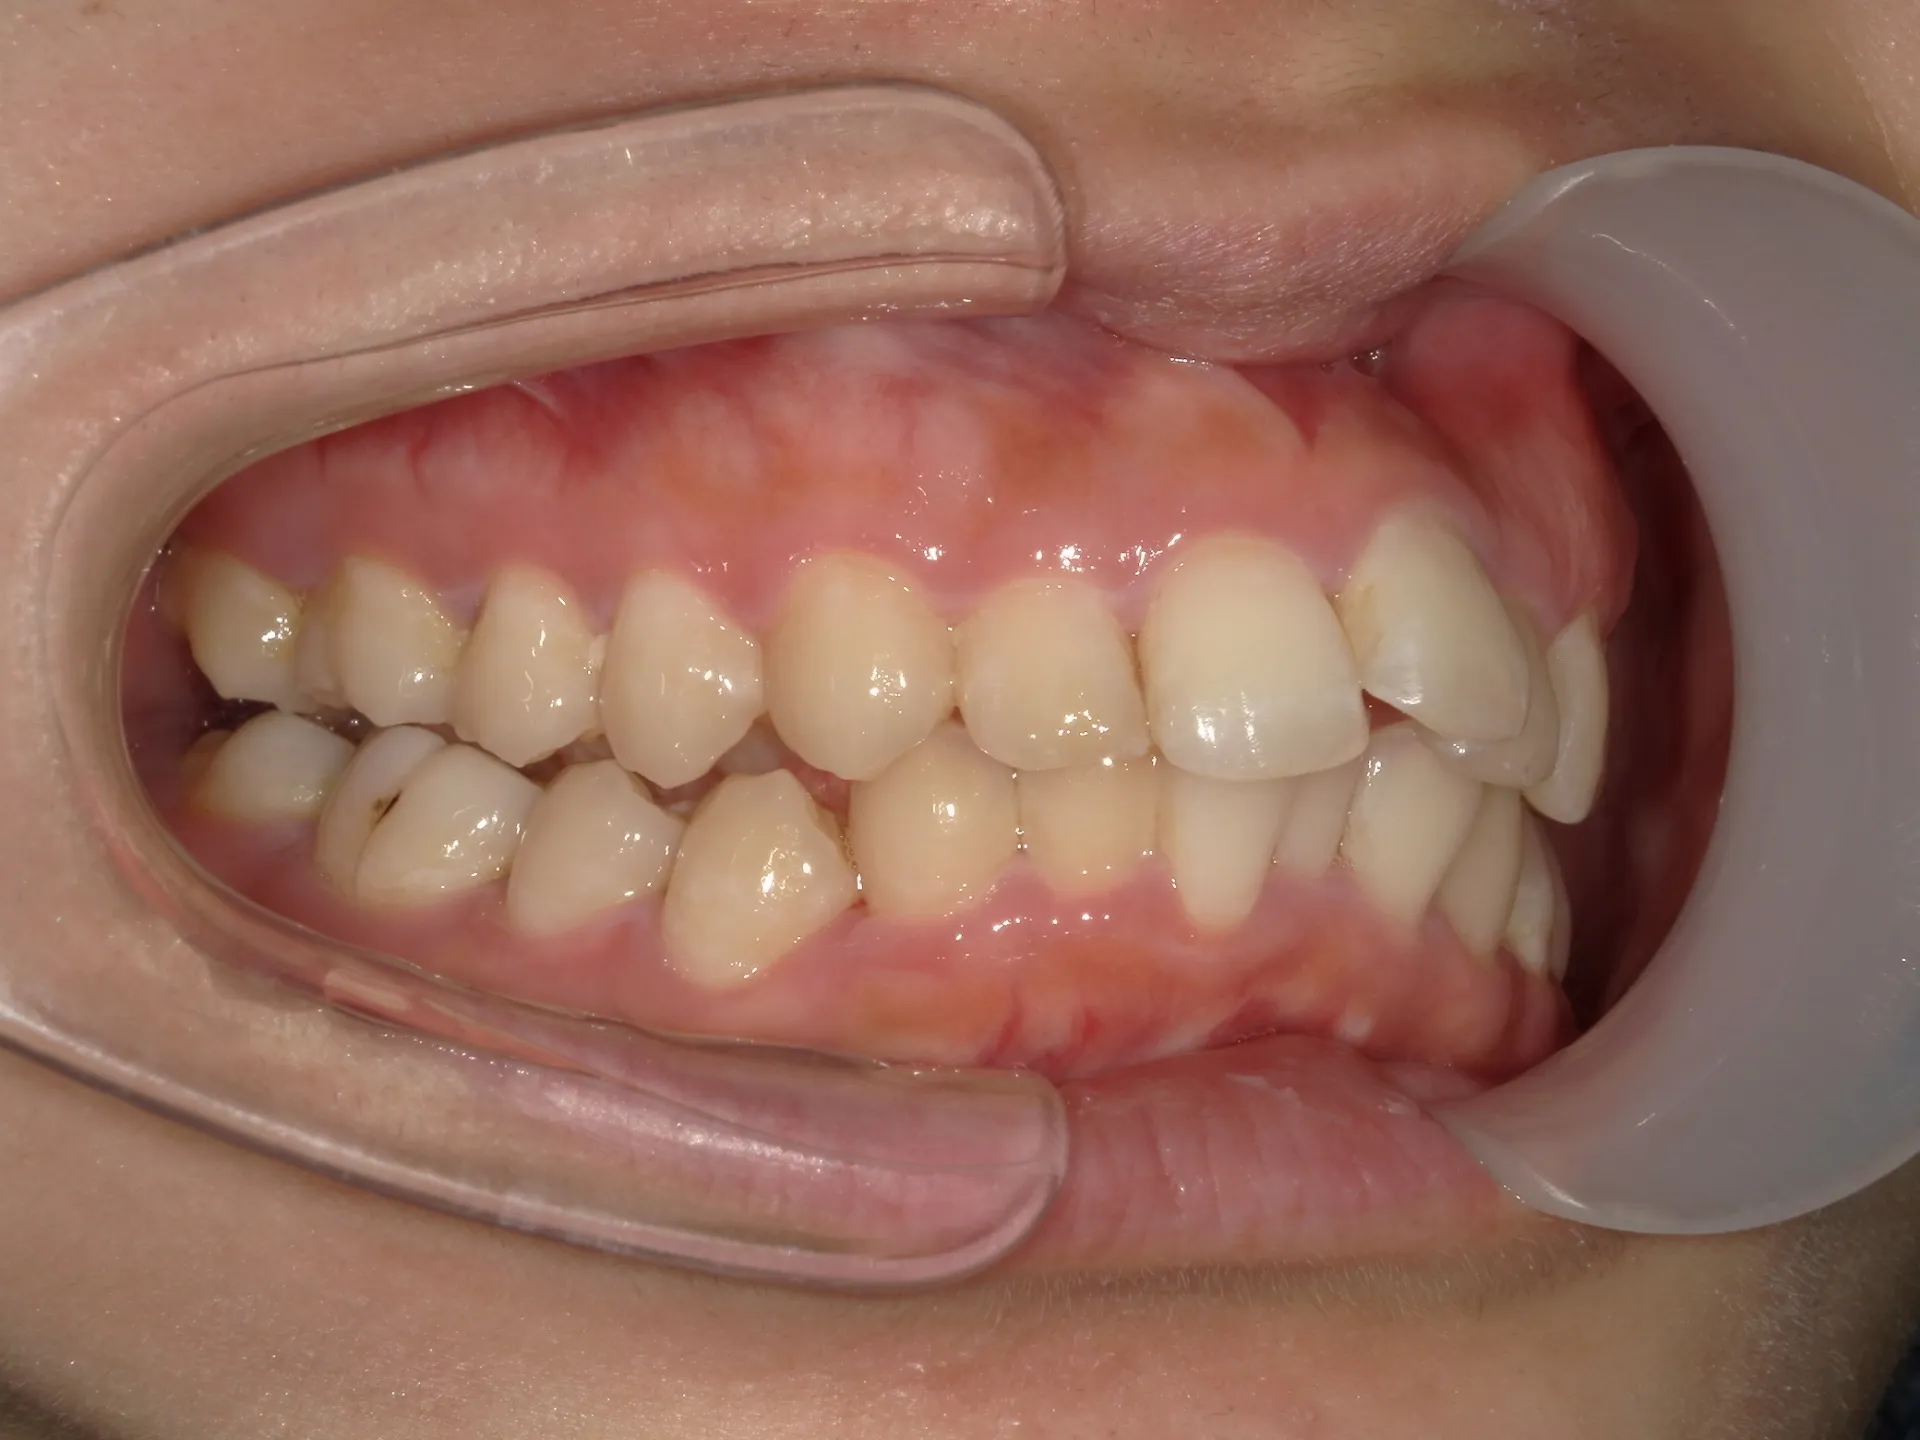

今回はマウスピース矯正(インビザライン)で前歯の出っ張りを治したケースをご紹介いたします。

マウスピース矯正で前歯の出っ歯感を抑えることが可能で、このケースでは上の歯のみ2本の抜歯を行っています。